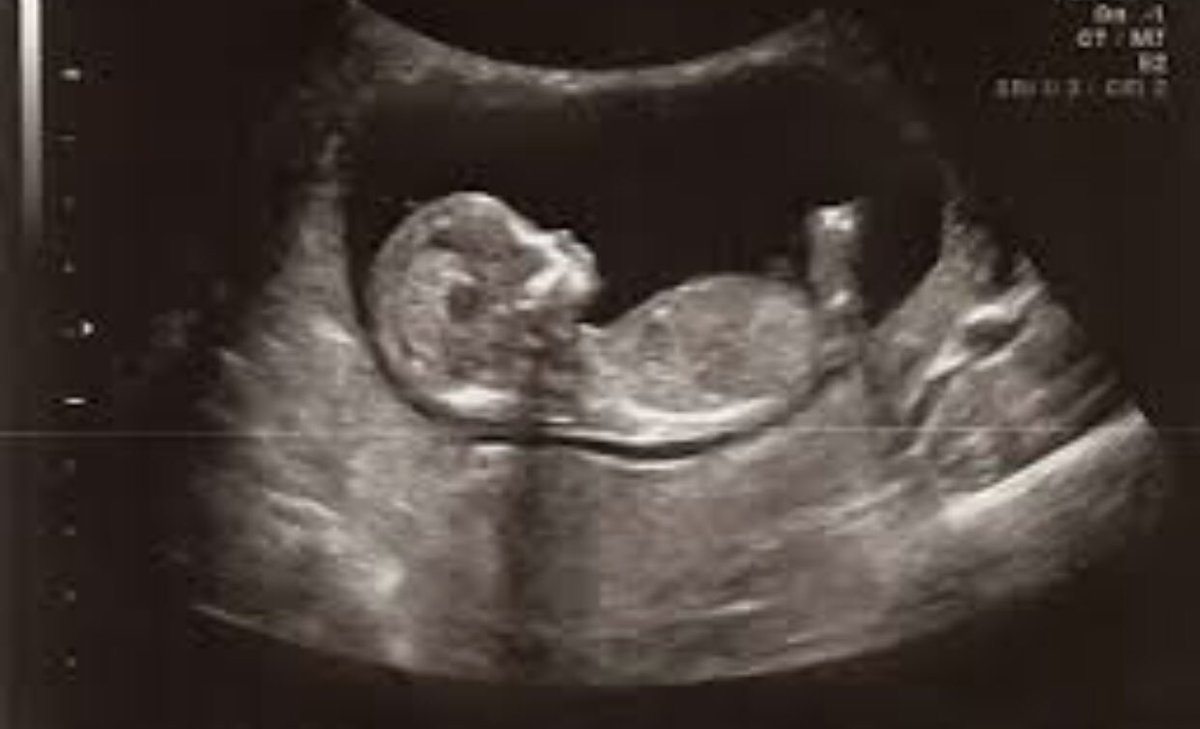

Ребенок в 13 недель